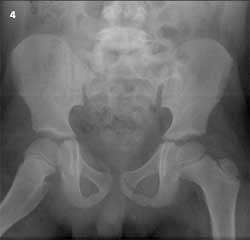

A 6-year-old boy was a passenger on an adult-sized ATV with his uncle. The ATV rolled over on both of them when the uncle lost control. The boy was wearing a chest protector at the time but no helmet. He sustained extensive injuries to both inguinal areas and to his mid-anterior thighs and lower legs. Figure 3 shows an angulated, displaced distal tibia as well as fibula fractures. CT scans and an anteroposterior radiograph of the pelvis (Figure 4) revealed bilateral nondisplaced pelvic bone fractures involving the right superior pubic ramus and bilateral inferior pubic rami. The open right tibia wound was extended surgically, irrigated copiously, and the fracture was reduced. Intravenous antibiotic therapy was administered for 48 hours. A drain was placed in the open wound, and the patient was placed in a long leg cast (Figure 5). The drain was removed in 2 days through an opening in the cast. The patient healed without complications.